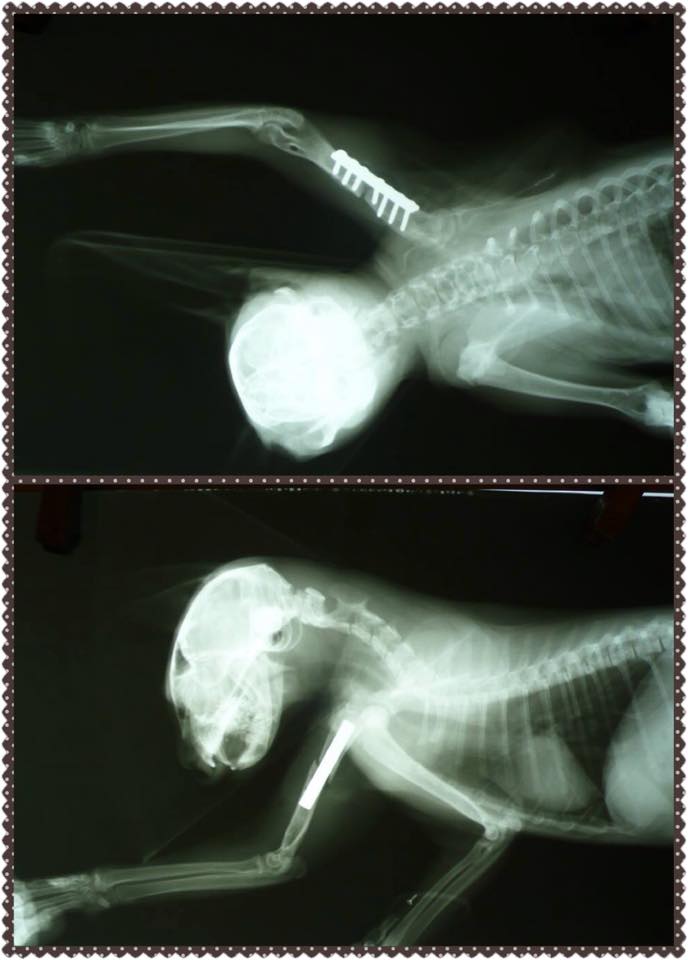

11/3晚上志工在誘捕貓咪時發現有隻大概5個月的小黑貓腳怪怪的,好像斷掉了,而且他處在的環境實在是很糟糕,需要跳上跳下,非常危險的高樓層,而且鄰居對流浪貓很不友善,怕是被人驅趕歐打所造成的傷害。

後來連同要結紮的貓咪還有受傷的貓咪一起送長沁動物醫院,拍了X光後,確診為右前腳上肢斷裂。